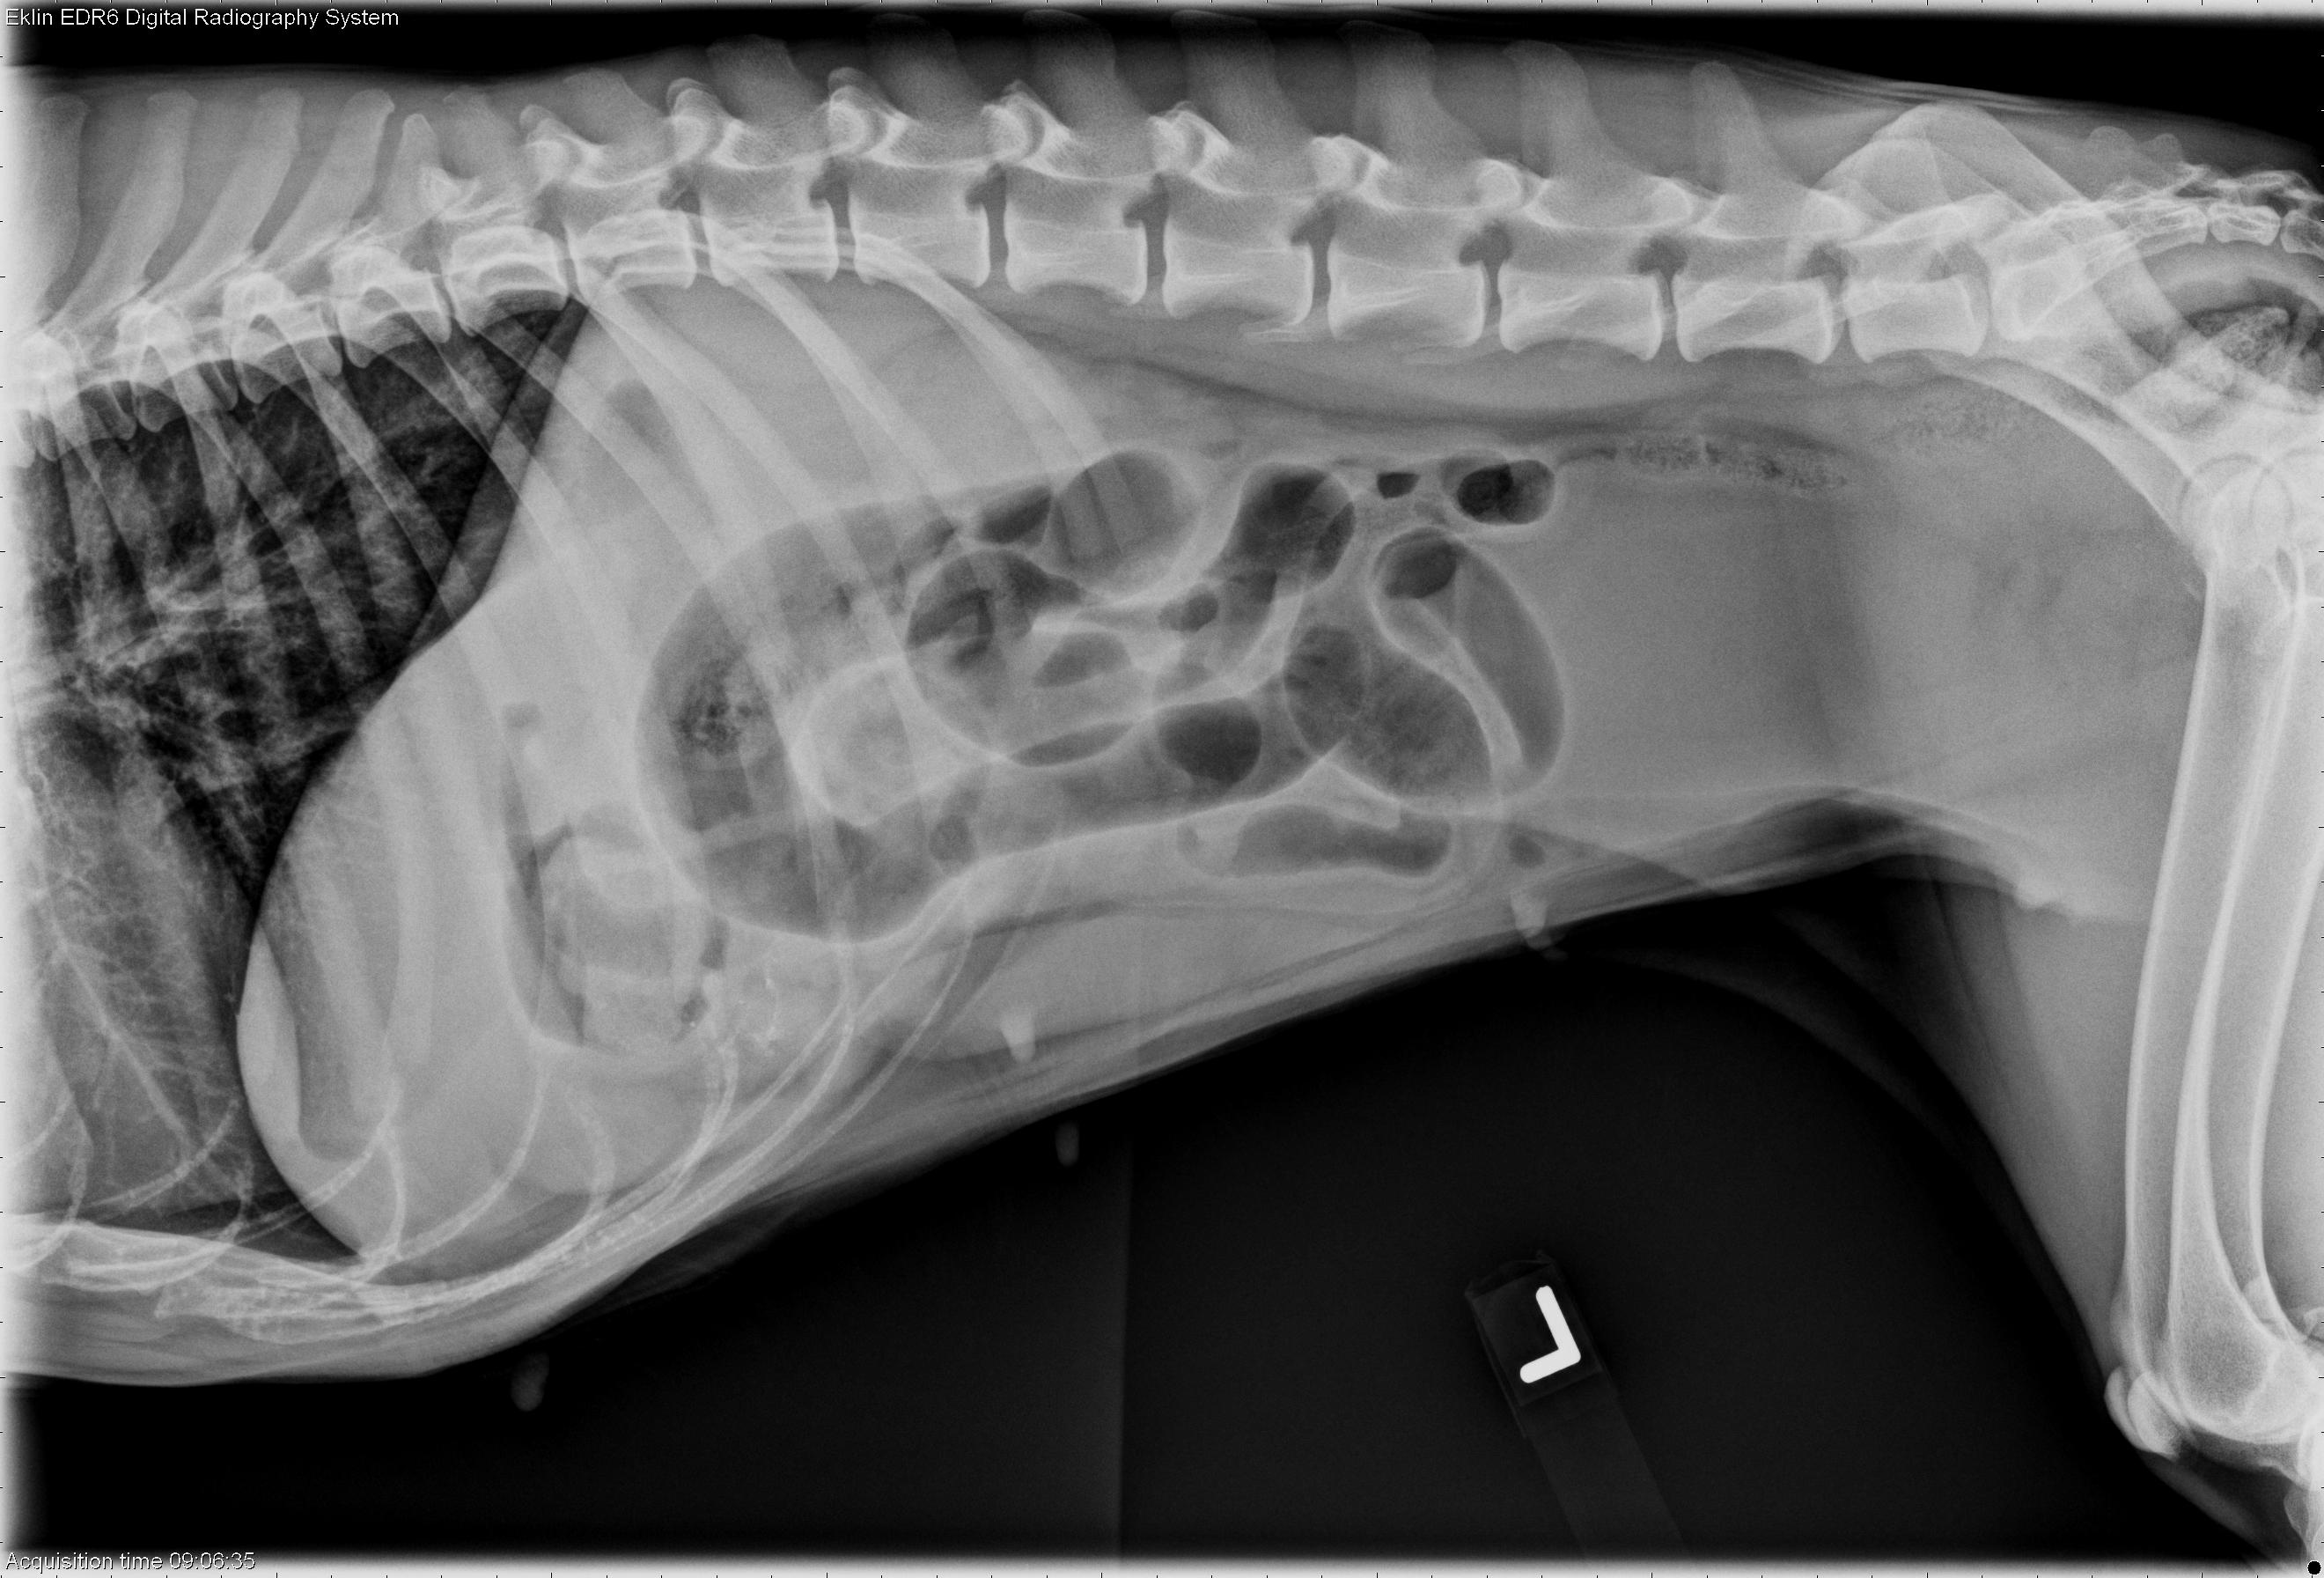

4 year old Brittany Spaniel

Happy New Year to all my VR readers! I hope you are feeling rested and recharged for the year ahead. On that note, enjoy this case! It is a 4-year-old Brittany Spaniel with one episode of vomiting, several incidences of diarrhea, anorexia, and lethargy for the last two days.

R LAT Abdomen

L LAT Abdomen

The duodenum plus additional small intestine are dilated with gas. On the right lateral projection, there are normally sized small intestinal loops visible.

Additionally, there is soft tissue opacity foreign material in the pylorus on the left lateral projection. It is suspended in the pylorus and surrounded by air.

Small intestinal obstruction, most likely due to foreign body

Foreign body in stomach and jejunum – corn cob

The foreign material in the stomach was indicative of a foreign body obstruction. The dilated small intestine was due to the more distal jejunal piece of corn cob. Pyloric obstruction often results in a more dilated and fluid filled stomach, except if the animal has been vomiting, or there is a partial obstruction.

The key to diagnosing this case is in observing the two distinct populations of small intestine; enlarged greater than 1.5x the height of a vertebral body, and more normal appearing intestine.

Ultrasound images confirm the presence of “hard shadowing”, or attenuating, foreign material in the small intestine. Gas generally produces “dirty” shadowing, or multiple reverberation artifacts.